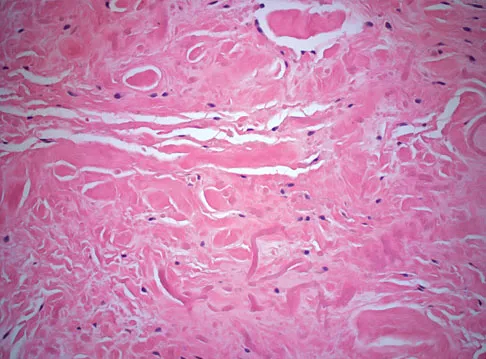

A 55-year-old woman has slowly increasing pain at the distal end of her little finger that is exacerbated by cold temperatures. She denies any history of trauma to her hands and is employed as a school teacher. The histology of the resected specimen is shown in Figure 71. What is the most likely diagnosis?

Explanation